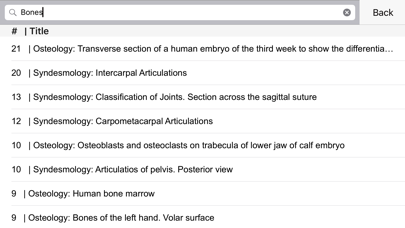

5. Explore resources quickly and easily with Wolfram Alpha, Wikipedia, Ask.com and other Medical Search Engines built right into the app.